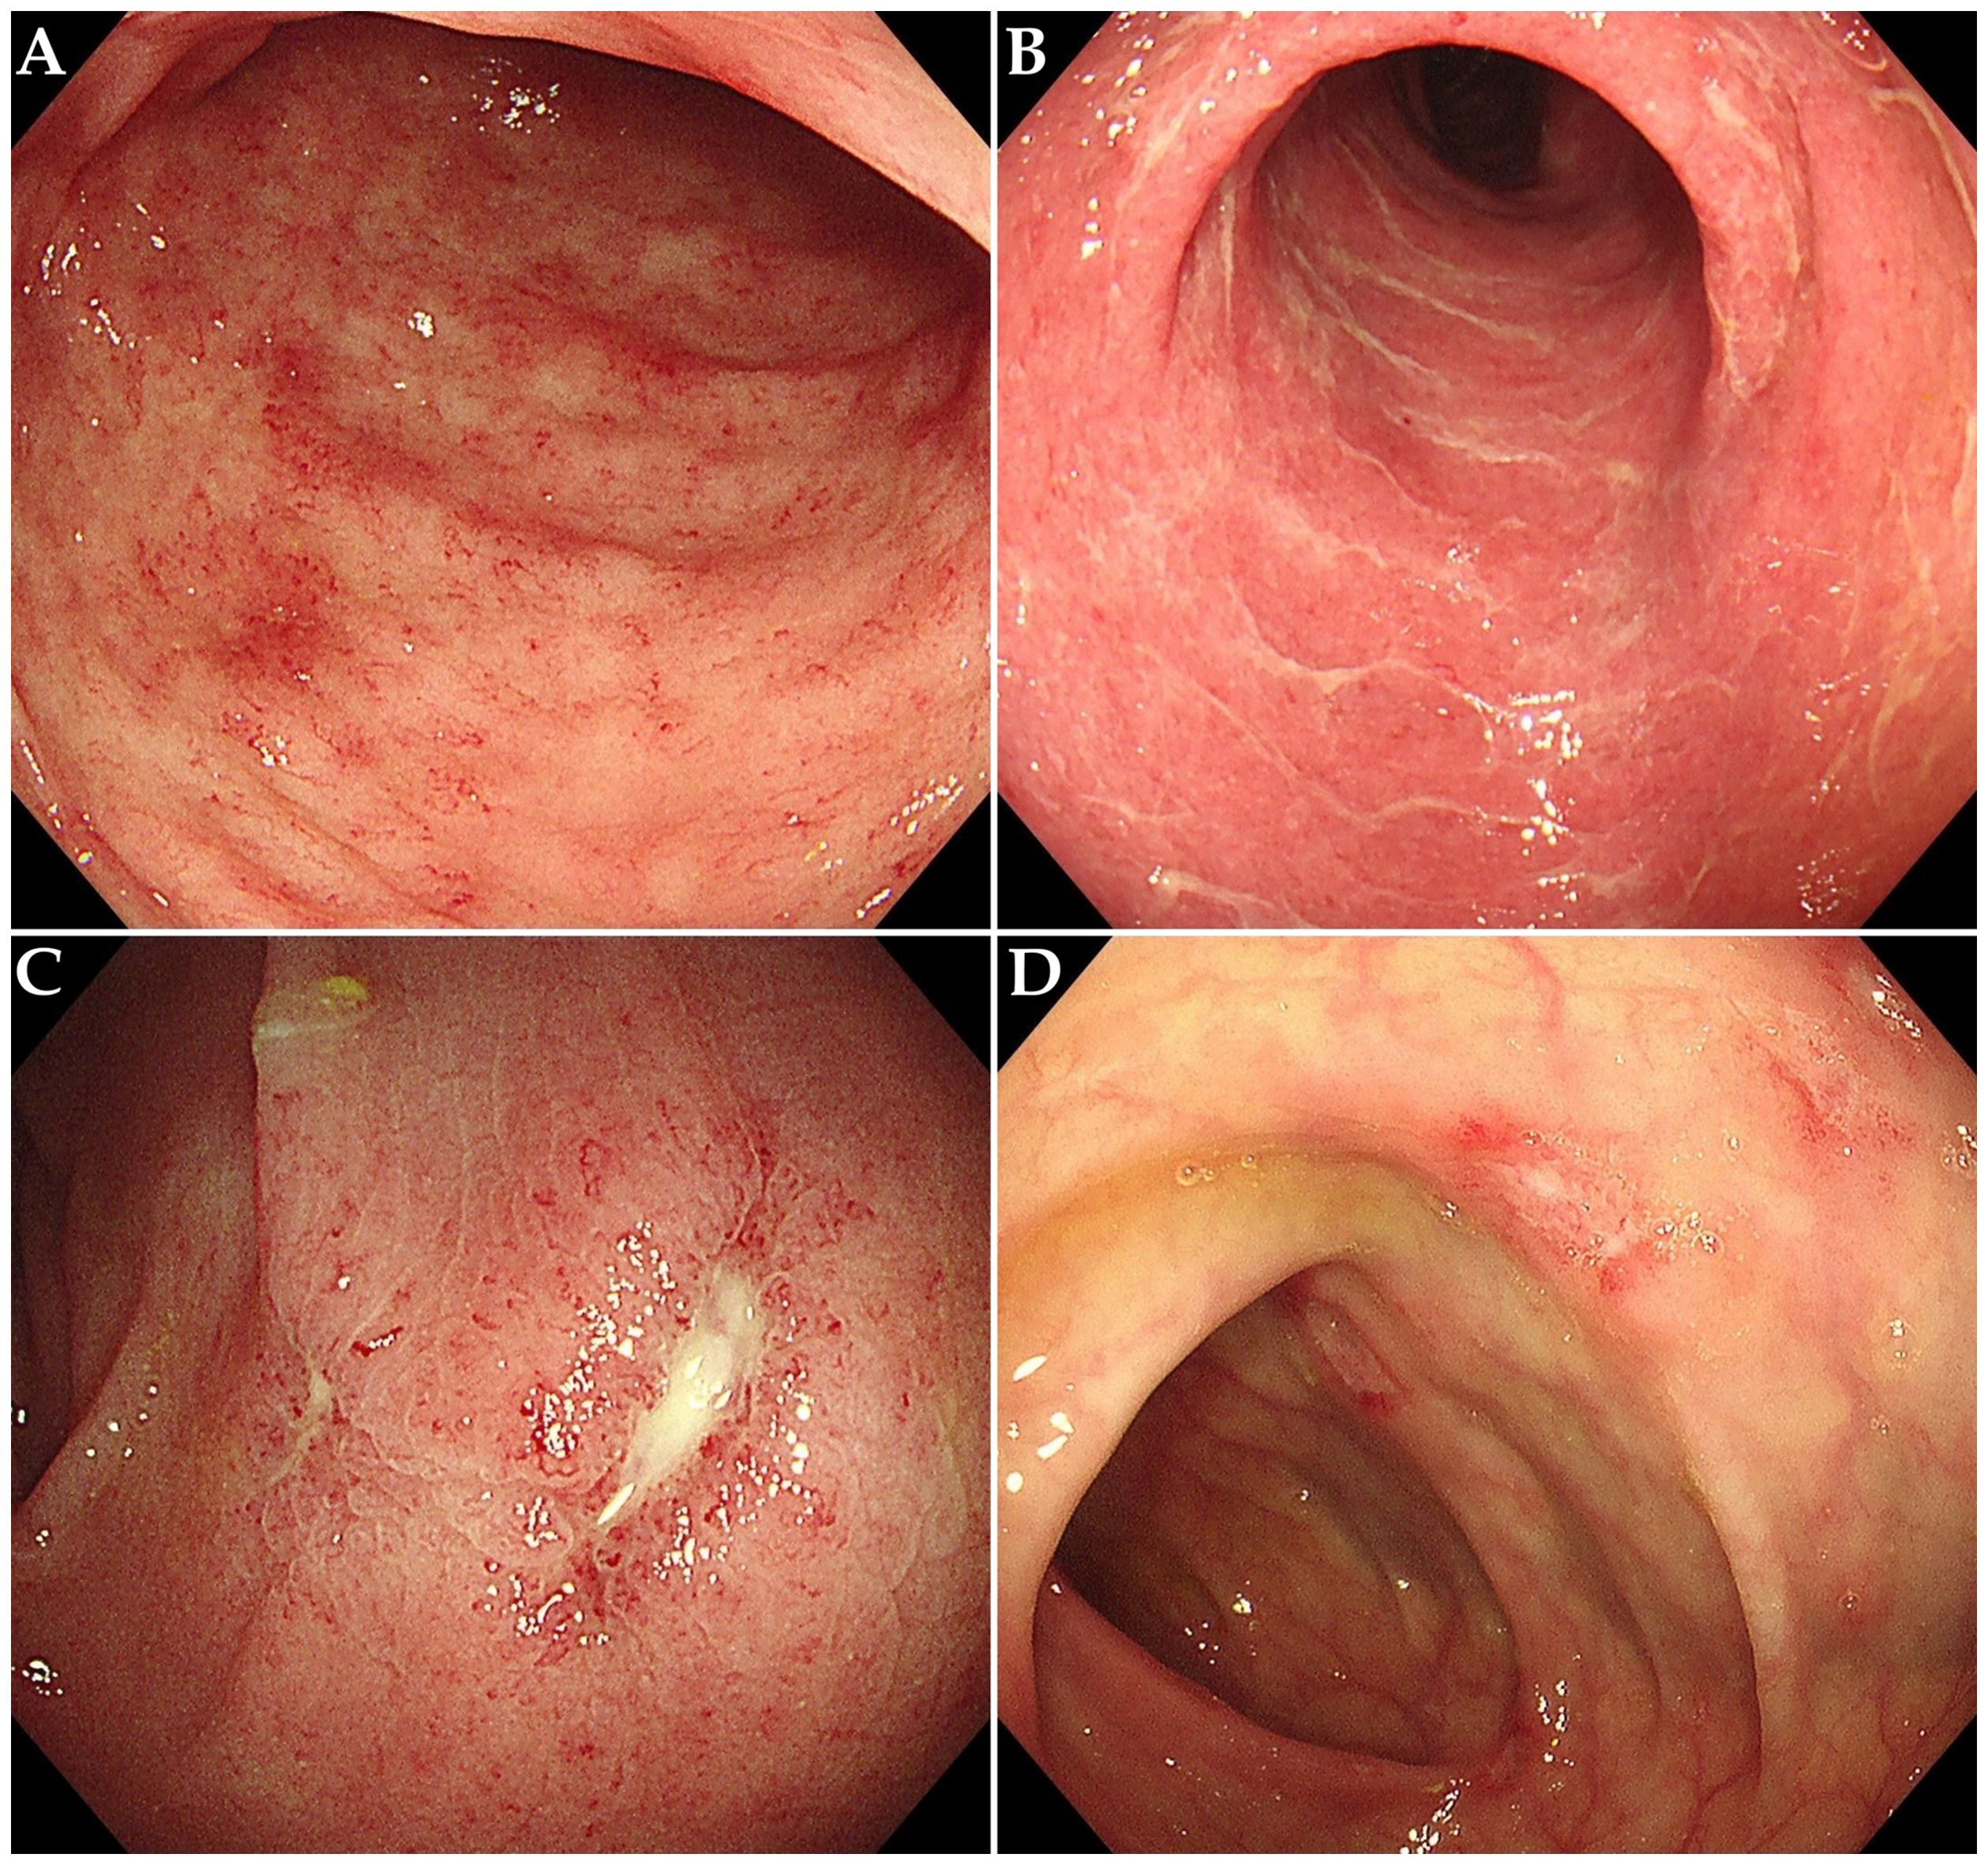

The characteristics of ICI-induced colitis are presented in Tables 1B, C. The median time to onset of colitis was 103 days (interquartile range [IQR] 52–142 days). The median number of ICI treatments received by patients before the onset of colitis was 5 (IQR 2-8). Diarrhea was the predominant symptom (n = 54, 94.7%), with many patients also experiencing abdominal pain (n = 32, 56.1%) or bloody stool (n = 28, 49.1%). Fever was observed in 5 patients (8.8%) at diagnosis. Among all patients, the number of cases with grade 2, 3, and 4 diarrhea was 17 (29.8%), 29 (50.9%), and 4 (7.0%), respectively. The number of cases with grade 2, 3, and 4 colitis was 39 (68.4%), 2 (3.5%), and 3 (5.3%), respectively. It is important to note that the grades of diarrhea and colitis may not be entirely consistent in many patients with ICI-induced colitis. Among the 26 patients who underwent colonoscopy, 10 patients (38.5%) showed non-ulcerative inflammation (such as mucosal edema, erythema, loss of vascular pattern, or increased friability, Figures 2A, B), while 16 patients (61.5%) presented with ulcerative lesions (Figures 2C, D). In terms of distribution, pan-colonic involvement was observed in 16 patients (61.5%), whereas partial colonic involvement (confined to either the left or right colon) was observed in 10 patients (38.5%).

Figure 2. Endoscopic features in patients with ICI-induced colitis. (A) Diffuse mucosal erythema with increased friability. (B) Mucosal edema, exudate and loss of vascular pattern. (C, D) Multiple ulcerative lesions.